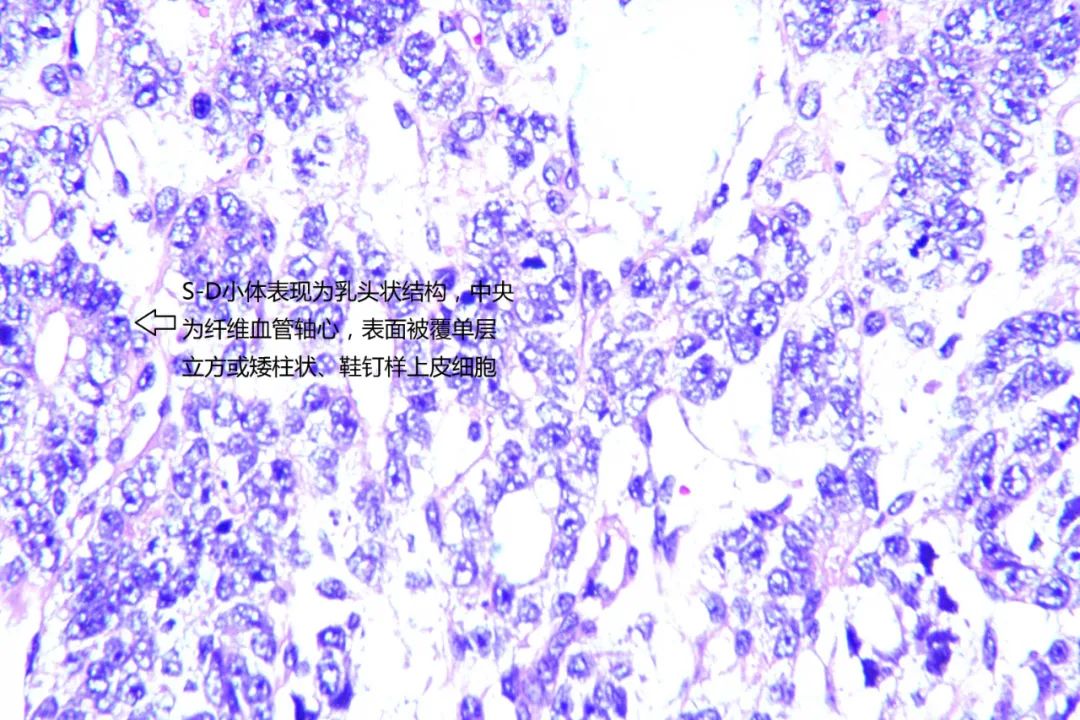

小颜在家人的陪同下来到我院妇科诊治,此时的小颜腹部已如孕6+月大小。住院后小颜莫名出现反复发热,抗感染治疗数日疗效欠佳。妇科主任米建锋经过系统全面的检查,考虑小颜的盆腹腔巨大肿物为卵巢恶性肿瘤的可能性极大,且发热考虑由该巨大肿瘤引起,建议尽快进行手术治疗。经与小颜家属沟通病情后决定行保留生育功能的手术治疗。术中发现巨大肿物来源于左侧卵巢,大小约25cm×20cm×12cm,包块与大网膜致密粘连,表面出血,腹腔内大量淡黄色积液约1500ml。在米建锋及普外科逄世江副主任医师的通力合作下,完整将小颜体内重二十余斤的肿物切除。米建锋表示,卵巢卵黄囊瘤又称内胚窦瘤,是一种原始生殖细胞肿瘤,恶性程度高,约占恶性卵巢生殖细胞肿瘤的20%,发病率仅次于无性细胞瘤,常见于儿童及育龄期女性,也有妊娠期发现。临床上由于肿瘤增长快,体积较大,又易有包膜破裂及腹腔内种植,往往起病急。腹痛是本病最常见的症状,肿瘤坏死、出血可使体温升高而有发热症状。首选的治疗方案为手术联合化疗,该肿瘤恶性程度高,但对化疗较敏感,手术恢复后可通过有效的联合化疗来延缓疾病的复发。